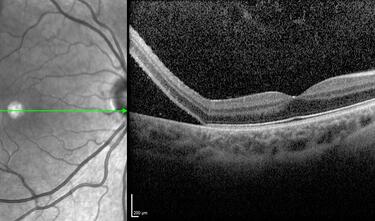

Clase 1 - Conceptos esenciales en fisiología y anatomía de la retina

Clase 18 - Signos estructurales diferenciales entre neurodegeneración y exudación en DMAE

Clase 20 - Signos clave en patología traccional vítrorretiniana